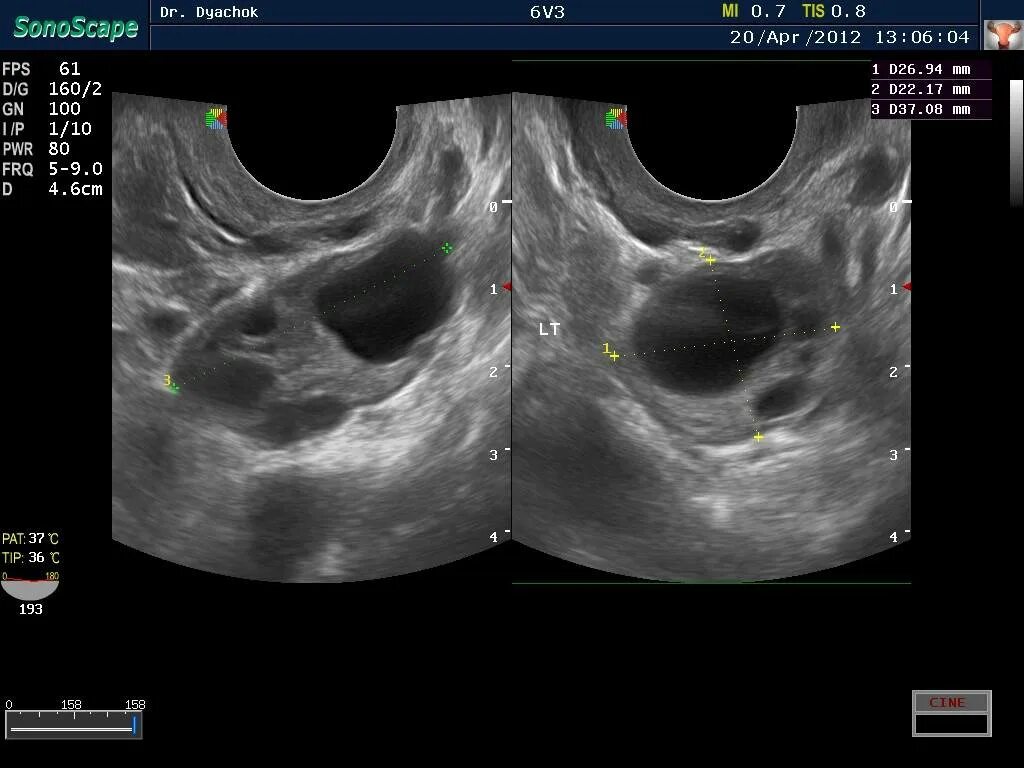

Когда делать узи яичников